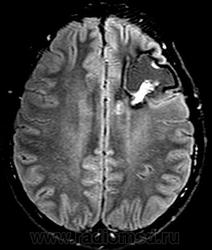

Внутрижелудочковая кавернома.